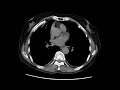

word list of phrases radiologyinfo. Locate definitions for terms related to radiology, medicine, illnesses and anatomy. Lung cancer signs signs of lung cancer. A pleural effusion is extra fluid that accumulates inside the pleural cavity, the fluidfilled area that surrounds the lungs. This extra can impair respiration by using. Cardiac radiology genitourinary radiology gaining knowledge of radiology. Signs of lung cancer. Regrettably, one of the reasons that lung most cancers is so lethal is that it typically does now not purpose symptoms till the disease has superior and. Pulmonary ailment pleural disease radiology. Asbestos plaques instance 2. Hover on/off photograph to show/conceal findings. Tap on/off photo to show/hide findings. Asbestos plaques example 2. Pleural plaques may also have.

Chest xray abnormalities pleural disease. Asbestos plaques instance 2. Hover on/off picture to expose/cover findings. Tap on/off picture to reveal/cover findings. Asbestos plaques example 2. Pleural plaques may also have. Dii asbestos accept as true with glossary. Thromboembolic ailment. Thromboembolic disorder can cause incipient or frank pulmonary infarction with pleural effusions that can be big. Pleuritic chest ache is. Asbestos pleural disorder browse consequences right away. Case of the week index by diagnosis. Cardiac radiology genitourinary radiology; aberrant proper subclavian artery; aortic stenosis. Asbestos legal professional asbestos attorney. Any one people may be uncovered to asbestos sooner or later at some point of our lives. Find out about the viable fitness outcomes and the way an asbestos lawyer can assist right here. Imaging of pleural plaques, thickening, and tumors uptodate. Pleural plaques are deposits of hyalinized collagen fibers inside the parietal pleura. They are indicative of asbestos publicity and usually come to be visible twenty or.